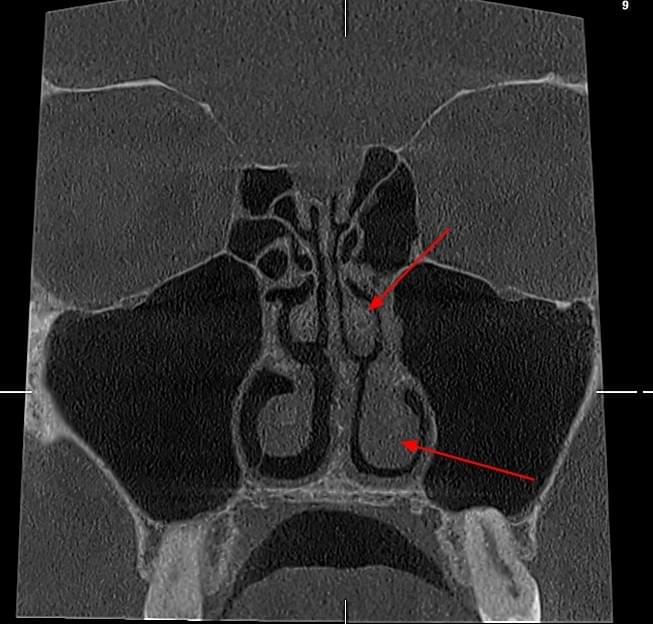

КПКТ (конусно-променева комп’ютерна томографія) — це 3D-знімок високої роздільної здатності. На відміну від звичайного рентгену, КТ показує:

Діагностика гайморових пазух за допомогою КТ

У сучасній медицині КТ придаткових пазух носа (або КТ синусів) — це «золотий стандарт»

діагностики для ЛОР-лікарів та щелепно-лицевих хірургів. Звичайний рентген часто не

показує повну картину, а МРТ не завжди доступний і дорожчий. Комп’ютерна томографія дає

детальну 3D-модель усіх пазух (гайморових, лобних, клиновидних та решітчастого

лабіринту) за 10 секунд і з мінімальною дозою опромінення.